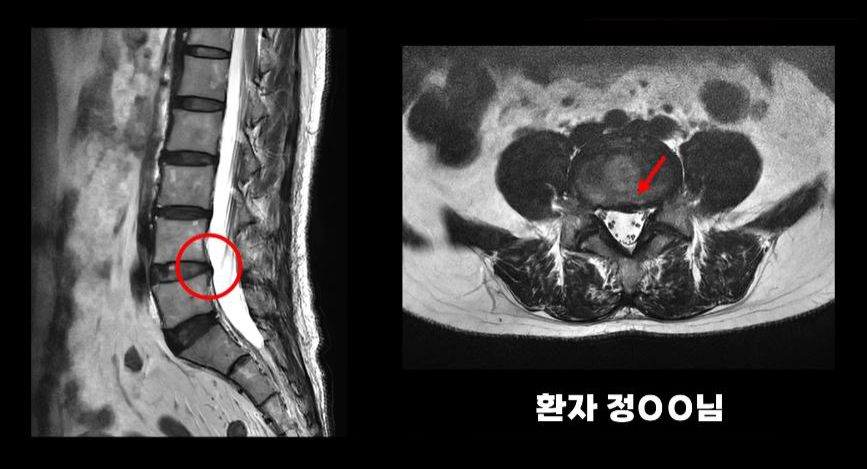

아래 환자분의 MRI를 보시길 바랍니다.

이분은 MRI상으로 신경 눌림이 그리 심해 보이지 않습니다. 그래서 여러 병원에서 디스크 문제가 아니라는 얘기를 들으셨는데, 이런 경우 디스크내장증이라고 말하는 의사들도 있습니다. 그런데 이 환자분은 근 감소와 근 기능 저하 등 근육 문제로 인한 심각한 근육성 방사통으로 원인이 밝혀졌고, 근육재활치료를 통해 좋아지셨습니다.